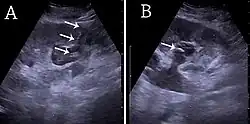

Cortical thickness should be estimated from the base of the pyramid and is generally 7–10 mm. If the pyramids are difficult to differentiate, the parenchymal thickness can be measured instead and should be 15–20 mm (Figure 3). The echogenicity of the cortex decreases with age and is less echogenic than or equal to the liver and spleen at the same depth in individuals older than six months. In neonates and children up to six months of age, the cortex is more echogenic than the liver and spleen when compared at the same depth.[1]

Figure 3. Measures of the kidney. L = length. P = parenchymal thickness. C = cortical thickness.[1]